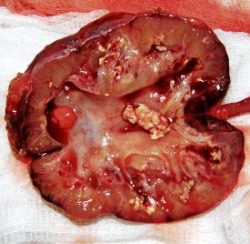

пионефроз - фотоПионефроз — гнойное расплавление ткани почки, превращение последней в мешок с гноем и детритом, являющееся, как правило, исходом активного течения вторичного (обструктивного) хронического пиелонефрита.

Клинико-рентгенологические признаки пионефроза достаточно характерны: почка прощупывается в виде плотного, малоподвижного и умеренно болезненного образования; при экскреторной урографии и радиоизотопной ренографии функция ее отсутствует; эхография дает картину большой полости; на ретроградных пиелограммах характерная картина резко расширенных полостей почки с неровными контурами (при калькулезном пионефрозе — контуры камней почки и/или камня в мочеточнике), при цистоскопии — выделение густого гноя из устья мочеточника (в виде «пасты из тюбика»).